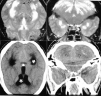

Fig. 2. La tomografía computarizada (TC) (imágenes superiores) evidencia lesiones isquemicoedematosas cerebelosas bilaterales (flechas), con comportamiento pseudotumoral y probable componente hemorrágico en el hemisferio izquierdo. A nivel supratentorial se constata una dilatación ventricular hidrocefálica (*) y una baja atenuación mal definida bioccipital. La resonancia magnética (RM) (imágenes inferiores) confirma y caracteriza con mayor sensibilidad estas lesiones isquemicoedematosas bilaterales occipitocerebelosas (caso 3).